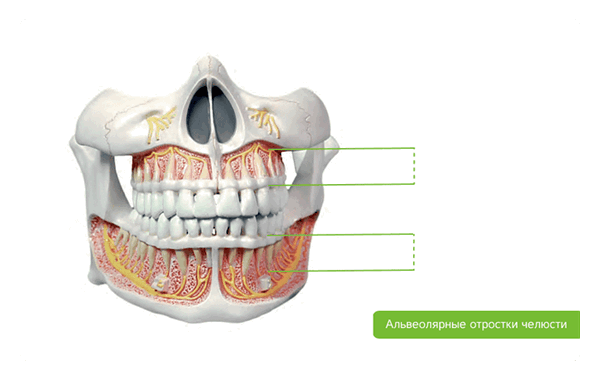

- изменилась форма альвеолярного отростка, что вызвало неустойчивость ортопедической конструкции;